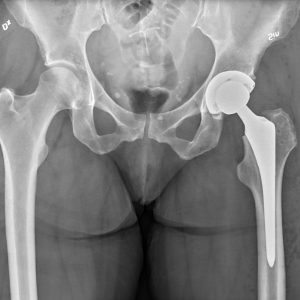

X-Ray Insights: Uncover the Need for Hip Replacement

Is an X-Ray Enough to Determine the Need for a Hip Replacement? Editor’s Notes: This article was published on [date] to provide valuable insights into the role of…